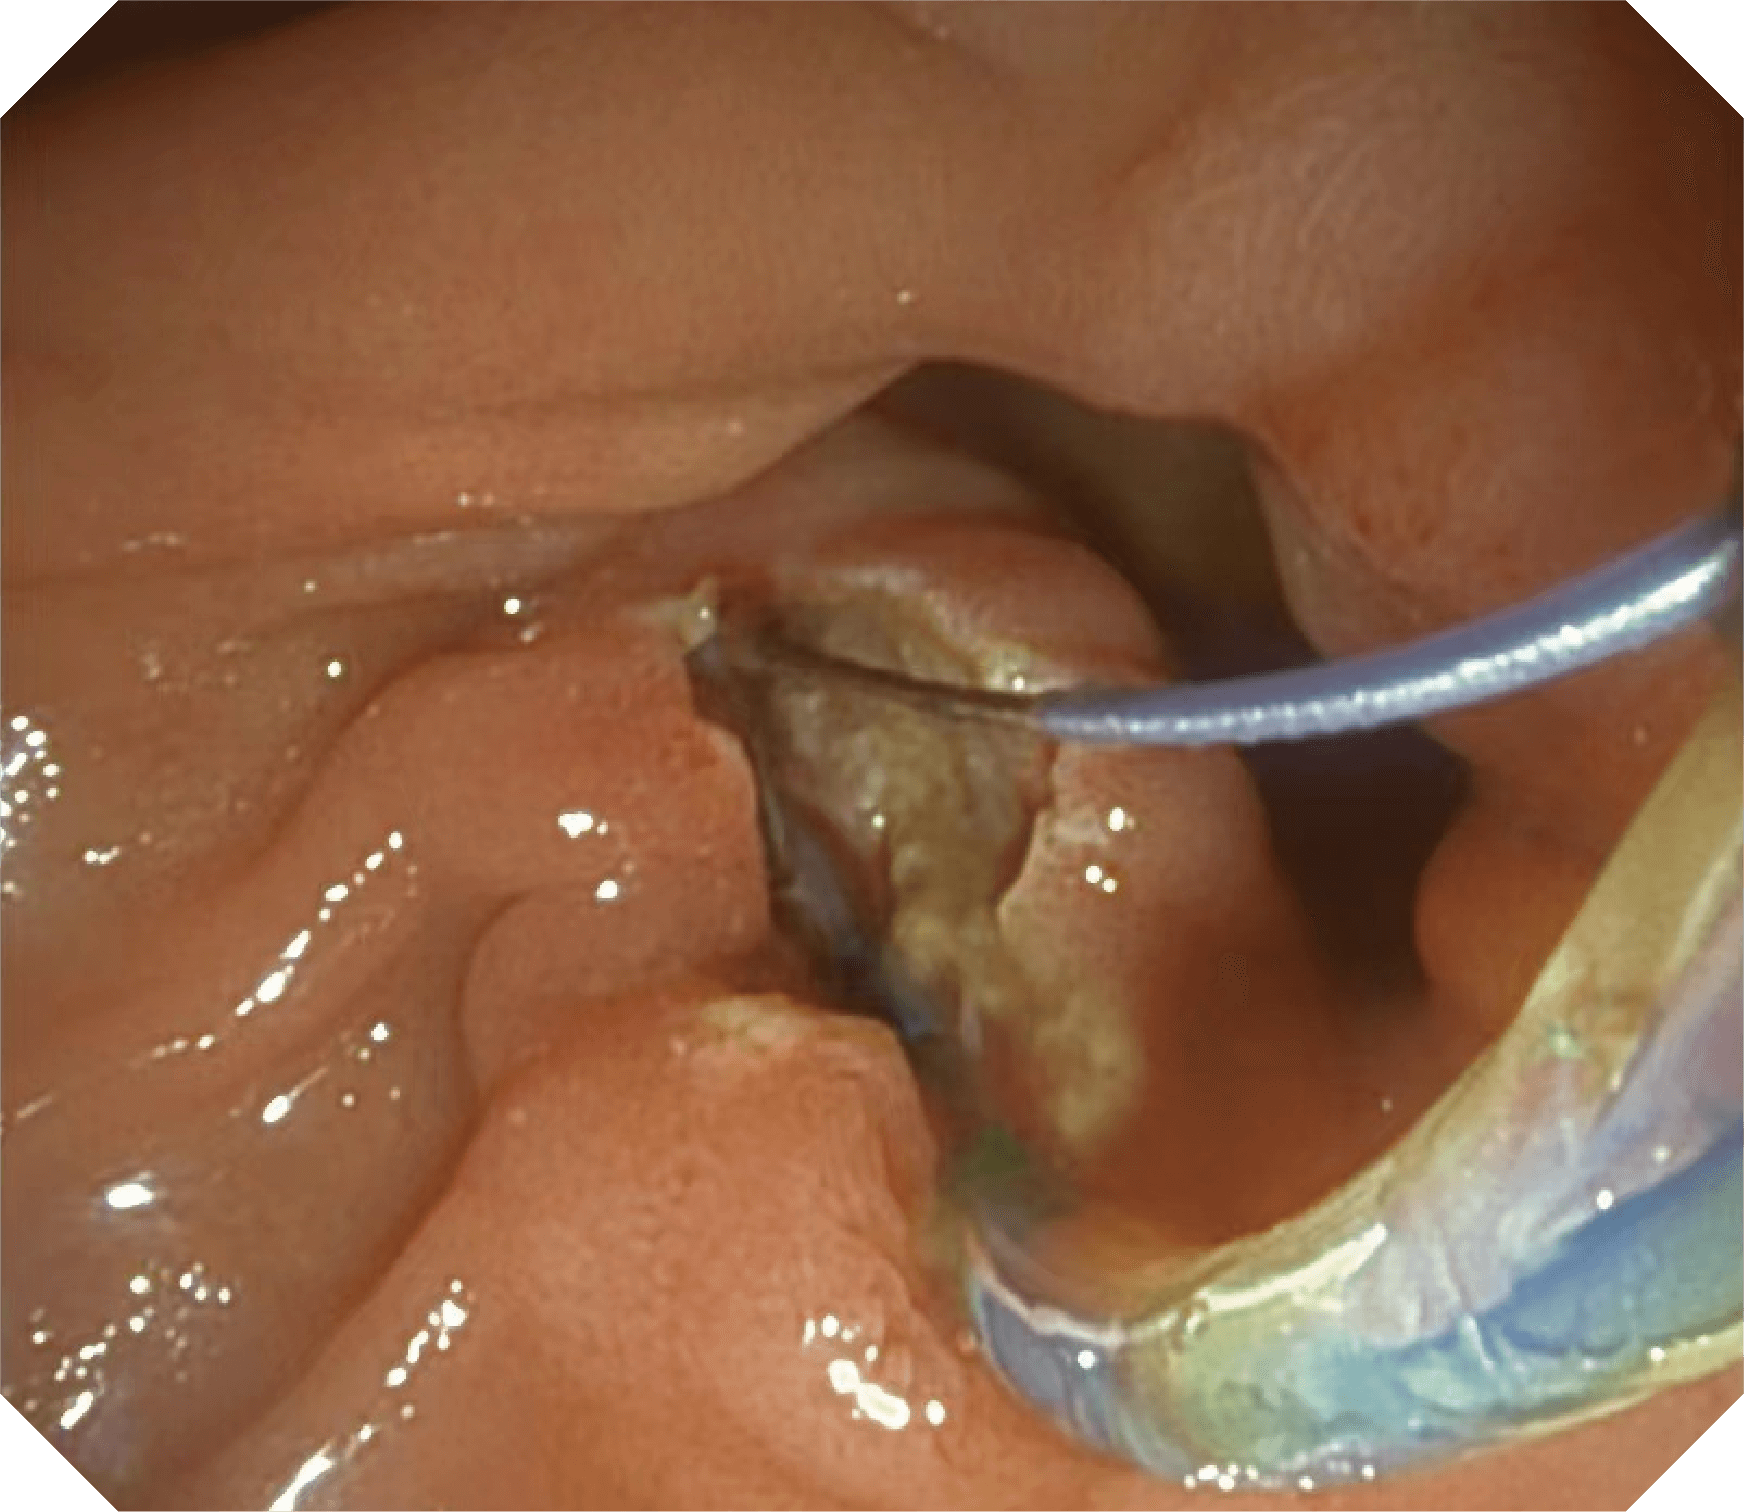

4.2mm大钳道,器械交换更顺畅

导丝机械锁紧功能

V槽设计提升导丝控制

优异的手术器械抬举性